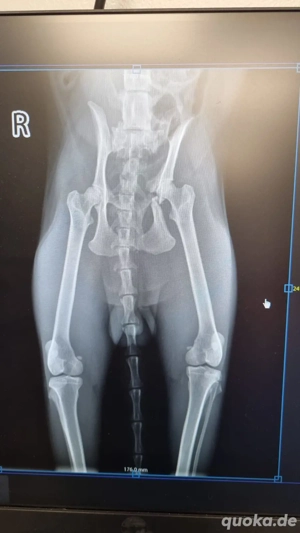

Vor etwa 3 Monaten wurde Batman leider von einem Auto angefahren. Zum Glück hat ihn eine liebe Dame gefunden, die ihm sofort zum Tierarzt brachte. Batman musste zweimal operiert werden. Anfang Dezember wurde die Platte entfernt. Die Fixierung mit Schrauben gehörte zur ersten OP.